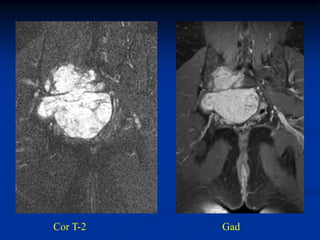

Cor T-2   Gad

Post op x-ray